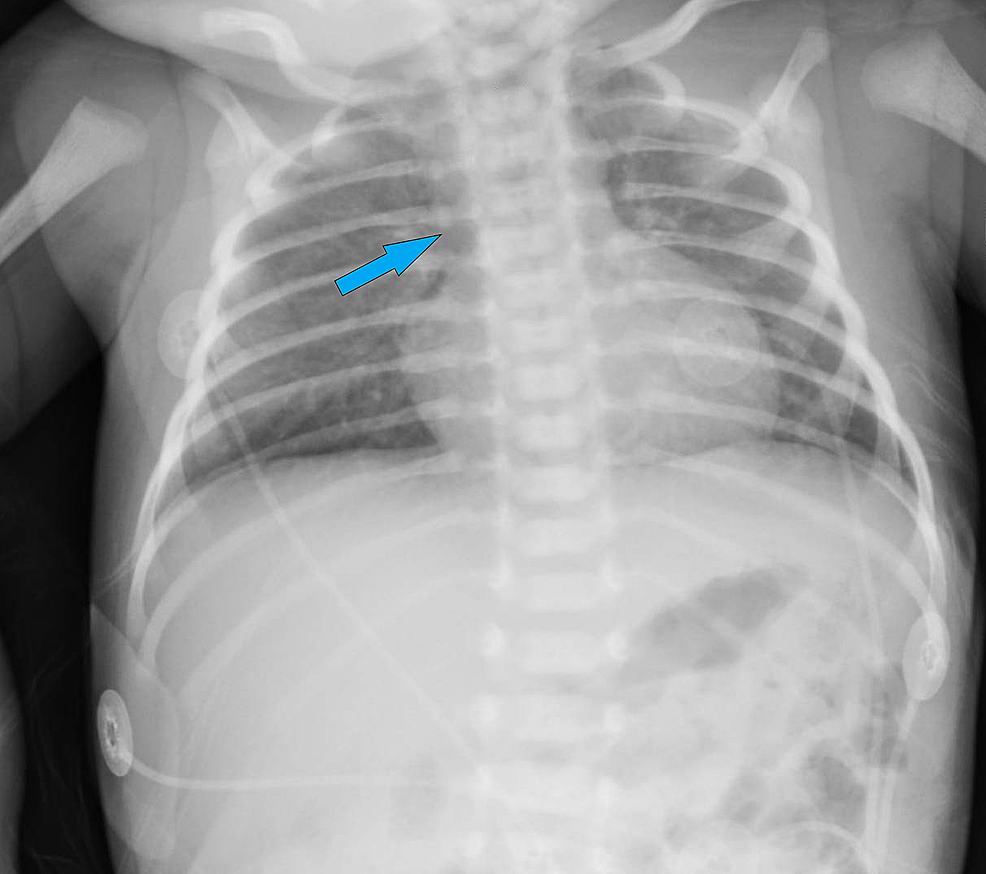

가슴샘이 없기 때문에, 흉부 X-ray를 찍어보면 정상적인 가슴샘의 음영 소실이 관찰됩니다 (Thymic shadow 없음)